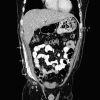

Dermatomyositis with extensive calcification in an adult

This report reviews a case of dermatomyositis presenting with weakness and extensive calcification in an adult. While dermatomyositis is not uncommon in adults, it is uncommon for calcifications to be present. Children develop calcifications more frequently than adults. When present in adults, small calcifications on areas of frequent trauma such as elbows and fingers are more common. However, this patient presented with large calcified deposits in his abdomen and extremities. His treatment and course are described.